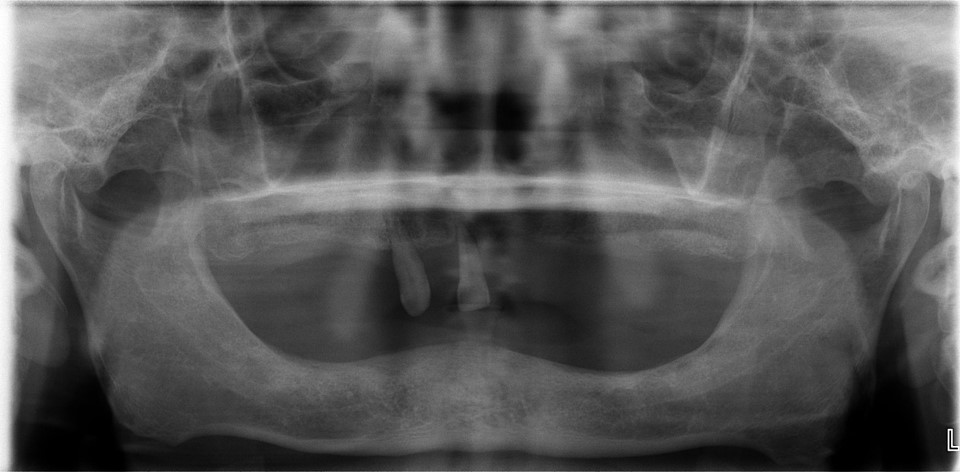

顯示出整個上顎骨或下顎骨。有時不能張 開囗,不能放置X光月在囗內,照射X光的患者, 也須要用這種口腔外 X光月的照相。這種 X光片能 檢查出在顎骨內的腫瘤、囊腫等惡性病質的疾病。